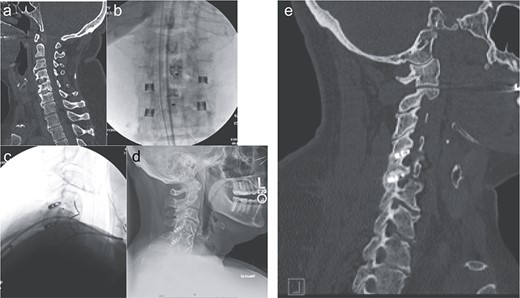

Imaging showing the minimally invasive interfacet cages technique. (a) Computer tomography imaging, sagittal view, showing lack of interbody fusion after ACDF 4-5-6. (b) AP intraoperative fluoroscopic images showing the placement of the interfacet cages. (c) Lateral intraoperative fluoroscopic images showing the placement of the interfacet cages. (d) Lateral X-ray showing a solid fusion at 1 year postoperatively. (e) Computer tomography imaging, sagittal view, showing a solid fusion at 1 year postoperatively.